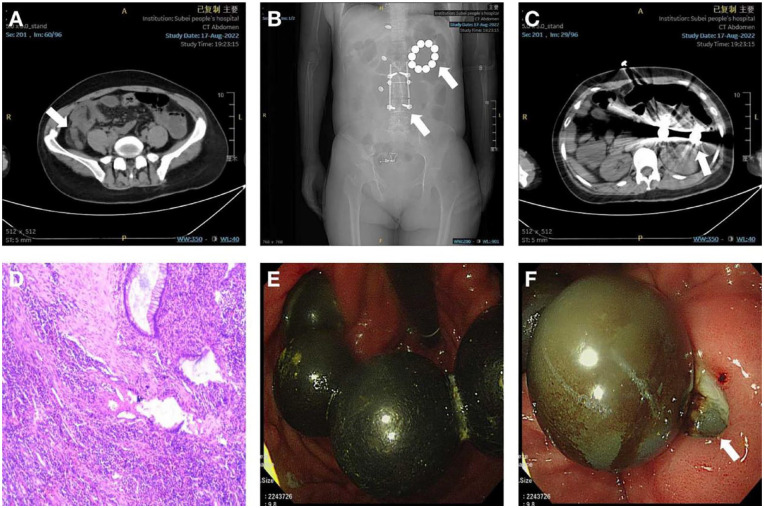

Presentation of case: We report an aschizophrenia female patient with onset of internal fistula across the posterior wall of stomach and the transverse colon triggered by swallowed magnetic metal beads. The patient was admitted to the emergency room of Northern Jiangsu People's Hospital because of acute right lower abdominal pain. Emergency routine abdominal CT scan revealed acute appendicitis and a set of foreign body in digestive tract.

Discussion: The foreign body in the stomach was removed by open surgery after tentative Endoscopic foreign body removal and laparoscopic appendectomy and exploration. In the process of exploring the gastric wall, it was found that one of magnet beads was embedded in the posterior wall of stomach and adhered to part of the transverse colon. After separation, it was found that an internal fistula was formed across the posterior wall of stomach and the transverse colon. As the patient ate only a small amount of food within 2 days, and the intestines were in good condition, we performed partial transverse colectomy, end-to-side anastomosis and gastric wall repair.

Conclusion: This case shows that for long-term foreign bodies in the digestive tract, we should be beware of the onset of gastrointestinal perforation. Moreover, perforation caused by the force acting on a blunt foreign body often results in atypical imaging findings, and the diagnosis of perforation cannot be clearly determined by imaging findings such as the presence of free gas downstream of the diaphragm. This poses new challenges for clear diagnosis and treatment.